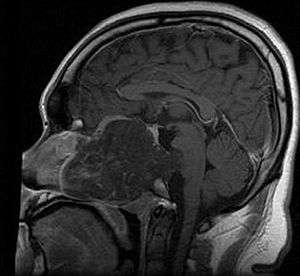

MRI of extensive clival chordoma in 17-year-old male patient, axial view. Tumor in the nasopharynx extending from nasal cavity to brainstem posteriorly is clearly visible. | |

Chordomas can arise from bone in the skull base and anywhere along the spine. The two most common locations are cranially at the clivus and in the sacrum at the bottom of the spine.[1]